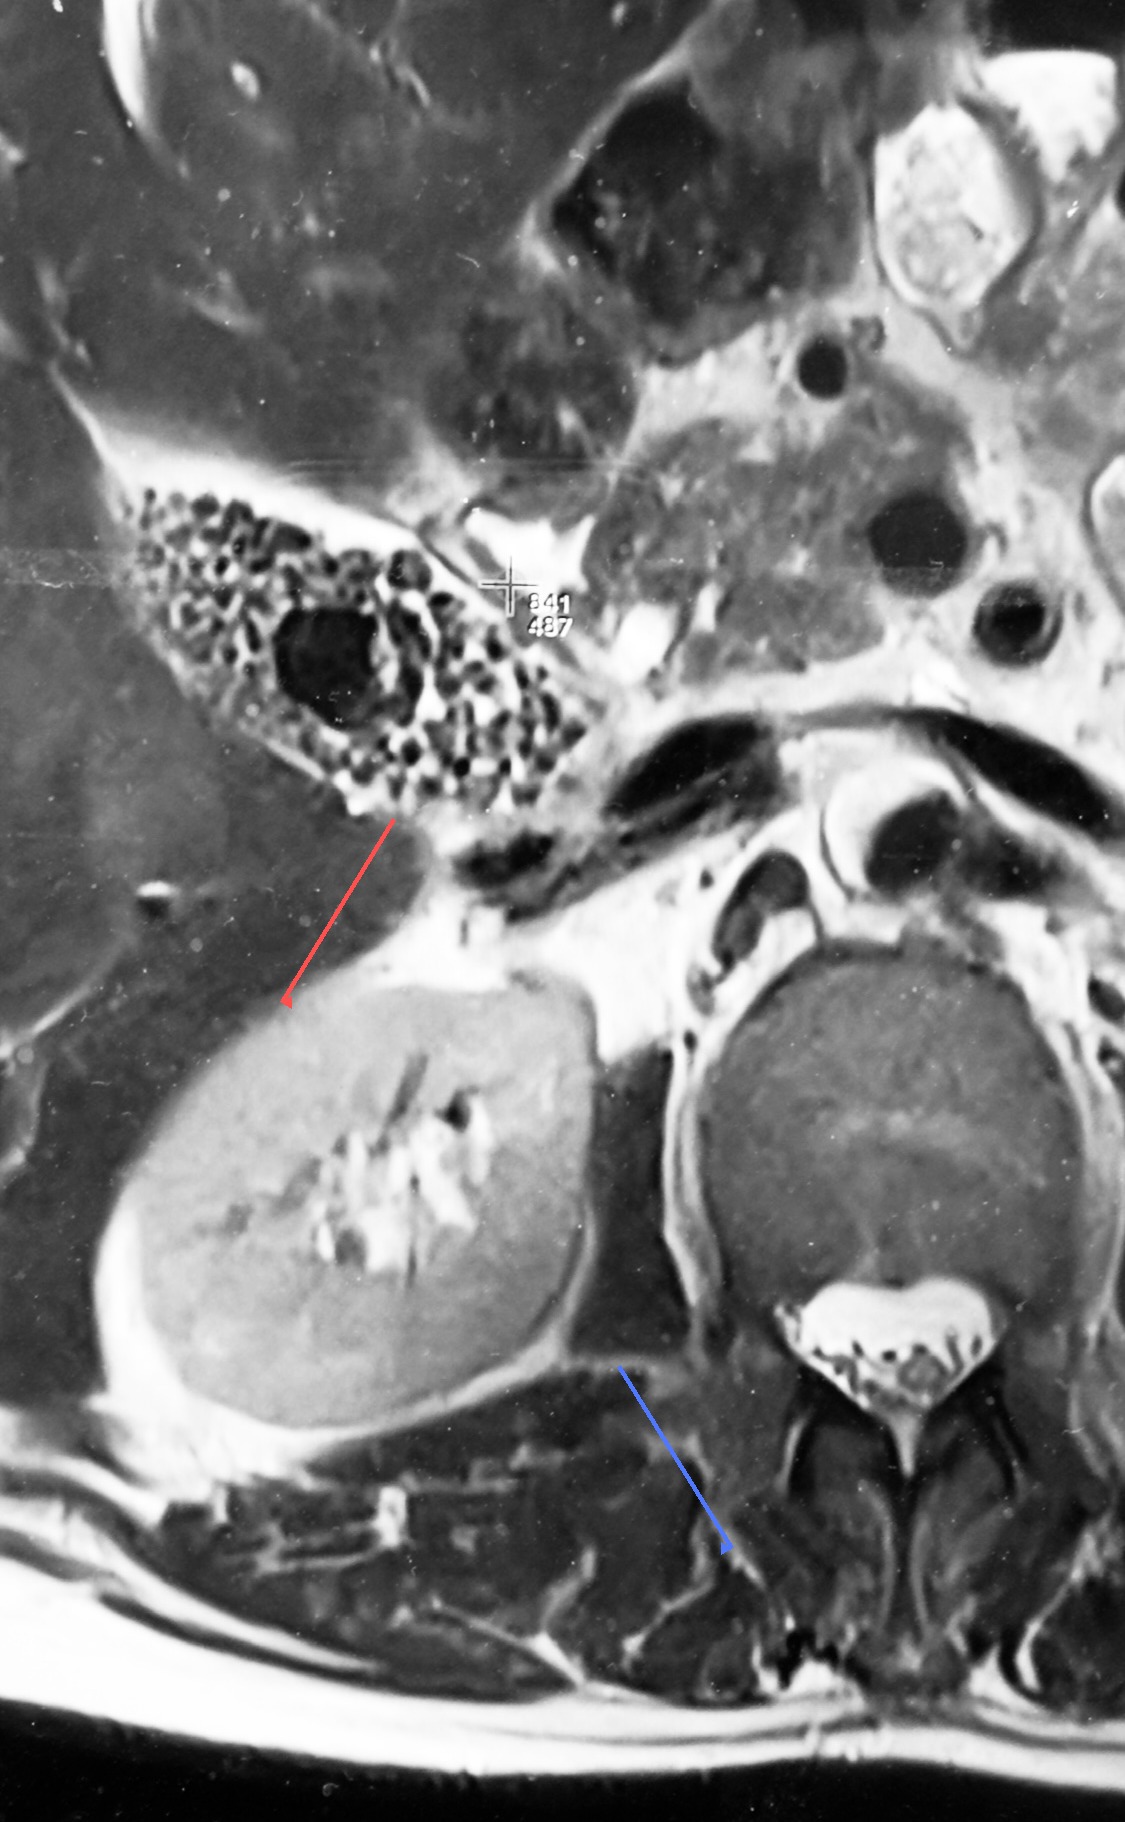

MRI scan showing gallbladder packed with gallstones (illustrative)

What this scan shows: The gallbladder (red arrow) is packed with gallstones — one large stone surrounded by many smaller stones (“gravel”). The kidney (blue arrow) is shown for orientation only and is normal.